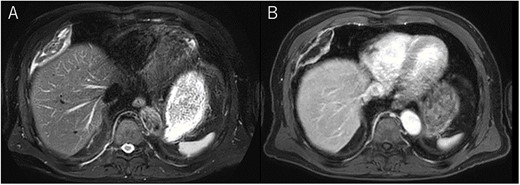

A 72-year-old man with a history of hypertension and left renal cancer (Stage I) was referred to us with a mass in the right chest wall on post-operative follow-up chest computed tomography (CT) for renal cancer. He had a smoking history of 20 pack-years and had no exposure to environmental fumes or dust. Physical examination results were unremarkable. The laboratory findings were within normal limits. Pulmonary function tests and cardiovascular examinations revealed normal results. Chest CT revealed mixed density mass (8.0 × 5.0 × 3.0 cm) located in front of thoracic wall in the third to sixth right intercostal space. The tumor can be revealed as thoracic wall fat (7.8 × 4.8 × 1.2 cm) on CT 1 year before (not considered as abnormal), and it was progressively increased in size and the density changed (Fig. 1A and B). Magnetic resonance imaging (MRI) showed a fatty mass of heterogenic density. T2 high foci (Fig. 2A) and irregular marginal enhancement of the tumor were observed (Fig. 2B). Maximal standard uptake value (SUVmax) of 18F-fluorodeoxyglucose positron emission tomography (FDG-PET) was 3.78 (Fig. 3). Based on these radiological image findings, we scheduled surgery with suspicion of liposarcoma. During the surgery, the patient was placed in the lateral decubitus position. We made 1.5-cm incision in the sixth intercostal space along the posterior axial line for thoracoscopy. We found dense adhesions between the chest wall tumor, lung (front part of all three lobes of the right lung) and diaphragm. We made a 30-cm incision in the fourth intercostal space and resected the tumor along with lung (wedge resection of the front part of all three lobes of the right lung), diaphragm and third to sixth ribs and intercostal muscle. The chest wall defect was 25 × 15 cm and the diaphragm defect was 8 × 5 cm. For reconstruction, the mesh was placed and sutured to the diaphragm and the chest wall. Pathological examination revealed the well-circumscribed tumor with fibrous adhesion between the ribs, lung and diaphragm (Fig. 4A). Microscopically, the tumor consisted of mature fat tissue. There were fat necrosis inflammatory changes in the marginal area of the tumor with foamy macrophages and multinucleated giant cells (Fig. 4B and C). Fluorescence in situ hybridization examination for murine double-minute 2 was negative. Based on these findings, a chest wall lipoma was diagnosed. The post-operative course was uneventful. The patient was followed up for 24 months without evidence of recurrence.

Chest MRI; (A) T2-weighted imaging showed several high signal foci in the tumor; (B) irregular marginal enhancement was observed.

Several critical radiological image findings have been reported for the differential diagnosis. Lipomas are discrete, encapsulated, homogeneous fatty masses on CT and MRI. On the other hand, thickened or nodular septa (>2 mm), prominent foci of high T2 signal and prominent areas of enhancement on MRI have been reported to be features suspicious of liposarcoma [5, 6]. In addition, tumor size >10 cm and fat content <75% have been reported as radiological features of liposarcoma [6]. SUVmax of FDG-PET reported that lipomas measured 0.8 ± 0.2 and well-differentiated liposarcomas measured 2.3 ± 1.2 [7].

In the present case, tumor enlargement with heterogenic change of the density, thickened septa >2 mm, prominent foci of high T2 signal and prominent areas of enhancement on MRI were seen on preoperative CT and MRI. In addition, the SUVmax of FDG-PET was higher than that of simple lipoma (SUVmax = 3.78). These findings led to a misdiagnosis for liposarcoma. Furthermore, intraoperative findings of dense adhesion between the tumor and surrounding structures strengthen our suspicion of liposarcoma. We could not find another case of intrathoracic lipoma of the chest wall with density change on radiological image and dense adhesion between the surrounding structures.